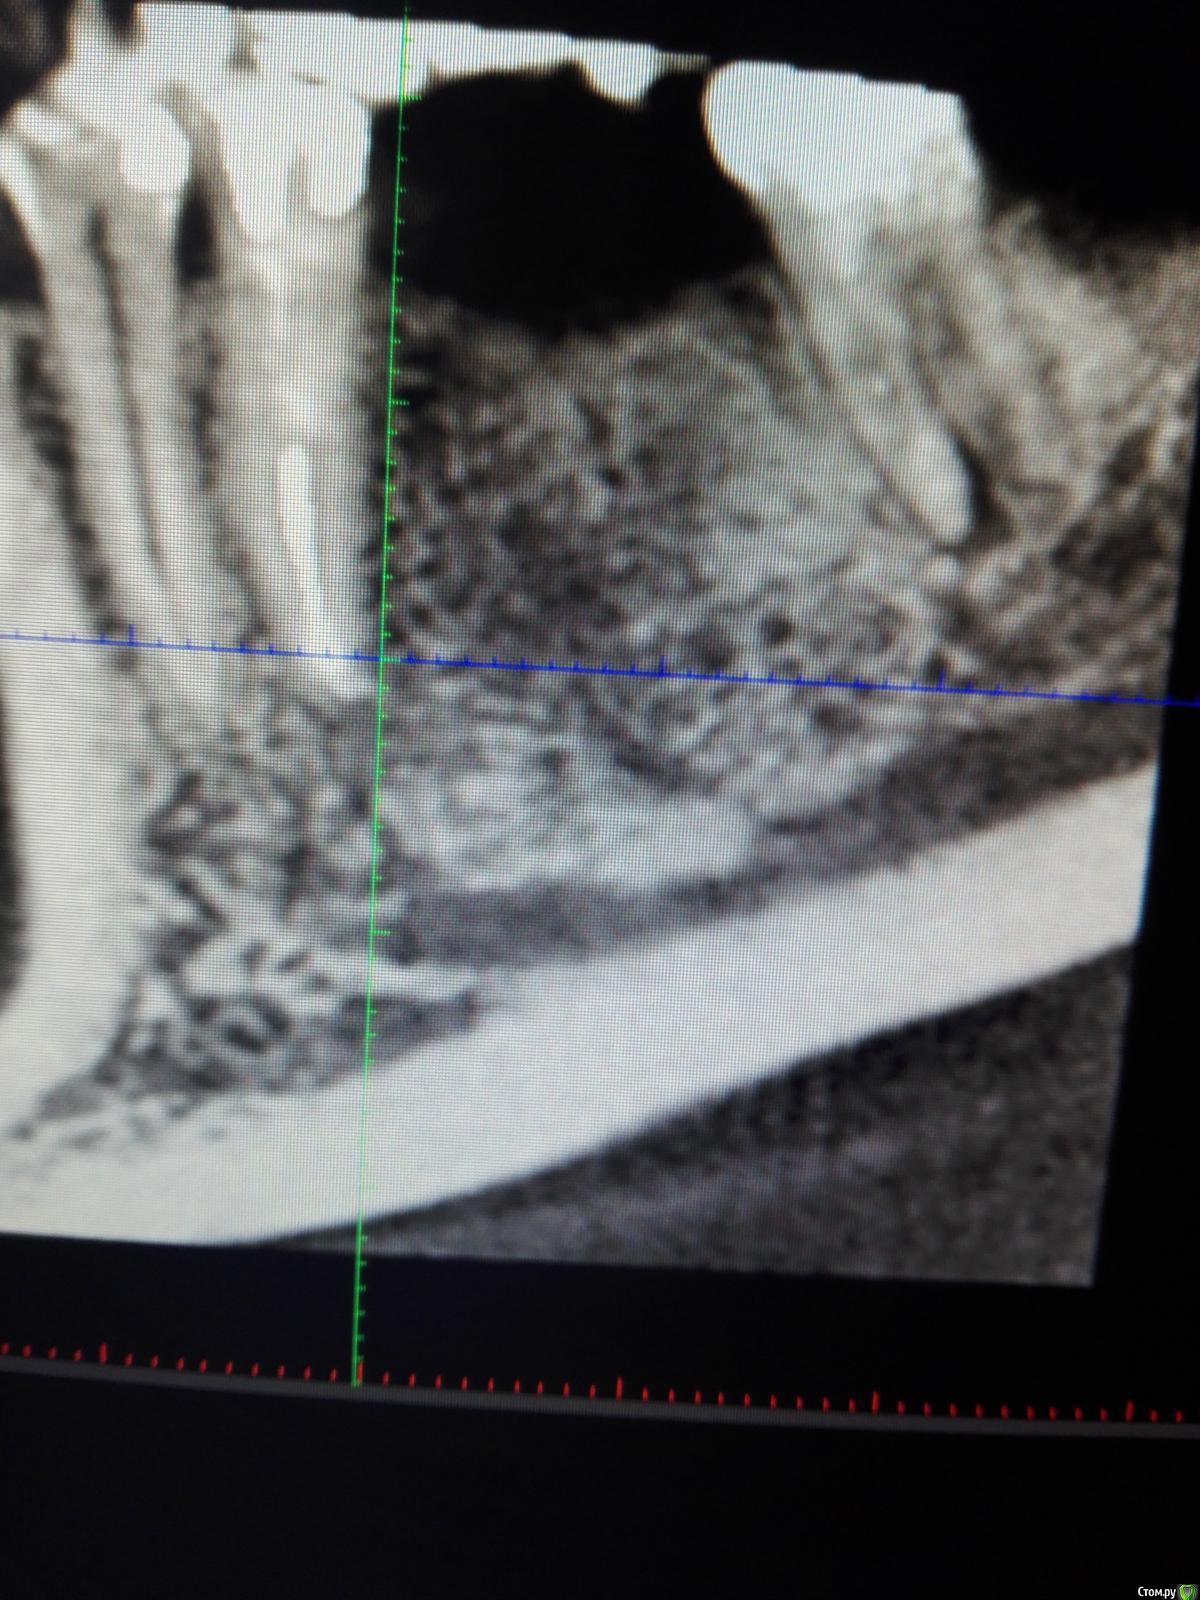

karasov Опубликовано 20 октября, 2016 Поделиться Опубликовано 20 октября, 2016 (изменено) В области 36 работал с ламиной. Наткнулся на нерв. Причем два. Один обошел , второй нет. Что ждать?на кт ееееле заметны Изменено 20 октября, 2016 пользователем karasov Ссылка на комментарий

kriokov Опубликовано 21 октября, 2016 Поделиться Опубликовано 21 октября, 2016 Наткнулся на нерв. не похож на нерв. имхо. Ссылка на комментарий

karasov Опубликовано 21 октября, 2016 Поделиться Опубликовано 21 октября, 2016 не похож на нерв. имхо.По кт есть однозначно связь с нижним альвеолярным. Визуально на сосуд не похоже Ссылка на комментарий

karasov Опубликовано 21 октября, 2016 Поделиться Опубликовано 21 октября, 2016 Слева был, справа есть Ссылка на комментарий

karasov Опубликовано 21 октября, 2016 Поделиться Опубликовано 21 октября, 2016 Обычно встречается первый тип, но у части населения бывает и второй..Или третий Ссылка на комментарий

koreandr Опубликовано 25 октября, 2016 Поделиться Опубликовано 25 октября, 2016 Это лунка заживает так Ссылка на комментарий

karasov Опубликовано 2 ноября, 2016 Поделиться Опубликовано 2 ноября, 2016 Это лунка заживает такне думаю,тк на кт с двух сторон Ссылка на комментарий